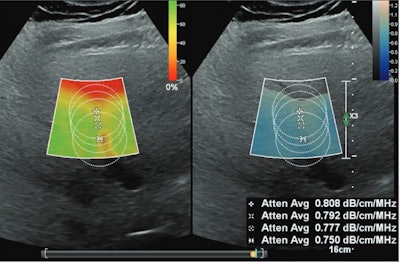

Ultrasound images depict a 56-year-old man with obesity (body mass index, 42) and steatosis (MRI-PDFF, 10.4%), who underwent ultrasound attenuation coefficient (AC) measurement due to participation in the present study. The unit displays color-coded confidence map (left) and AC map (on right) in side-by-side manner. The confidence map indicates quality of acquired AC signals and is set like traffic lights: green indicates good quality acquisition, yellow indicates warning, and red indicates low quality. Areas with low quality are left blank on the AC map. The image shows multiple circular ROIs placed at depths below the liver capsule of 2, 2.5, 3, and 4 cm. All ROIs are 3.5 cm in size. The confidence map threshold is set at 20%. AC measurements (in units of dB/cm/MHz) were extracted from all ROIs (excluding voxels without assigned color on the AC map) and decrease with greater ROI depth.ARRS